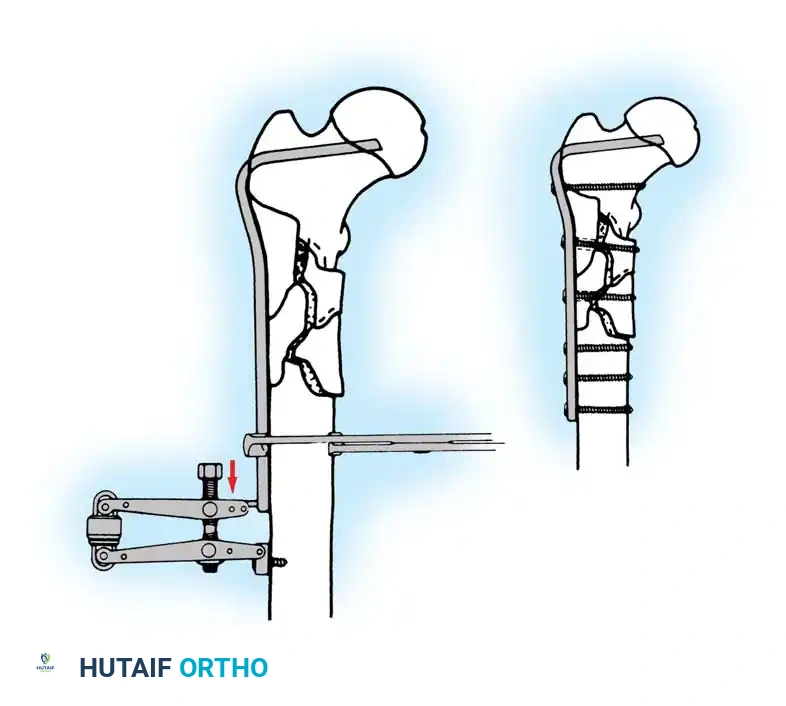

Implant Selection: SHS vs. Cephalomedullary Nail

- Sliding Hip Screw (SHS): The gold standard for stable intertrochanteric fractures (Evans Type I, AO 31-A1). The SHS allows controlled dynamic collapse along the axis of the femoral neck, compressing the fracture site and promoting primary bone healing.

- Cephalomedullary Nail (CMN): The implant of choice for unstable patterns, particularly reverse obliquity (AO 31-A3) and fractures with subtrochanteric extension. The intramedullary position of the nail decreases the lever arm of the implant, reducing bending moments and the risk of hardware failure.

Biomechanical Pearl: In reverse obliquity fractures, an SHS is contraindicated. The sliding mechanism of the SHS allows the femoral shaft to medialize uncontrollably due to adductor pull, leading to catastrophic failure. A cephalomedullary nail acts as a lateral buttress, preventing this medialization.

5. Intramedullary Nailing (For Unstable Fractures)

If a cephalomedullary nail is chosen, the entry point is established at the tip of the greater trochanter (or slightly medial, depending on the specific implant design).

Insertion of the cephalomedullary nail down the femoral shaft. Care must be taken not to distract the fracture site during insertion.

After the nail is seated, the proximal lag screw(s) are inserted through the nail into the femoral head, adhering to the same TAD principles.

Proximal locking of the cephalomedullary nail. The targeting guide ensures accurate trajectory into the femoral neck.

Finally, distal locking screws are placed to control rotation and maintain length.